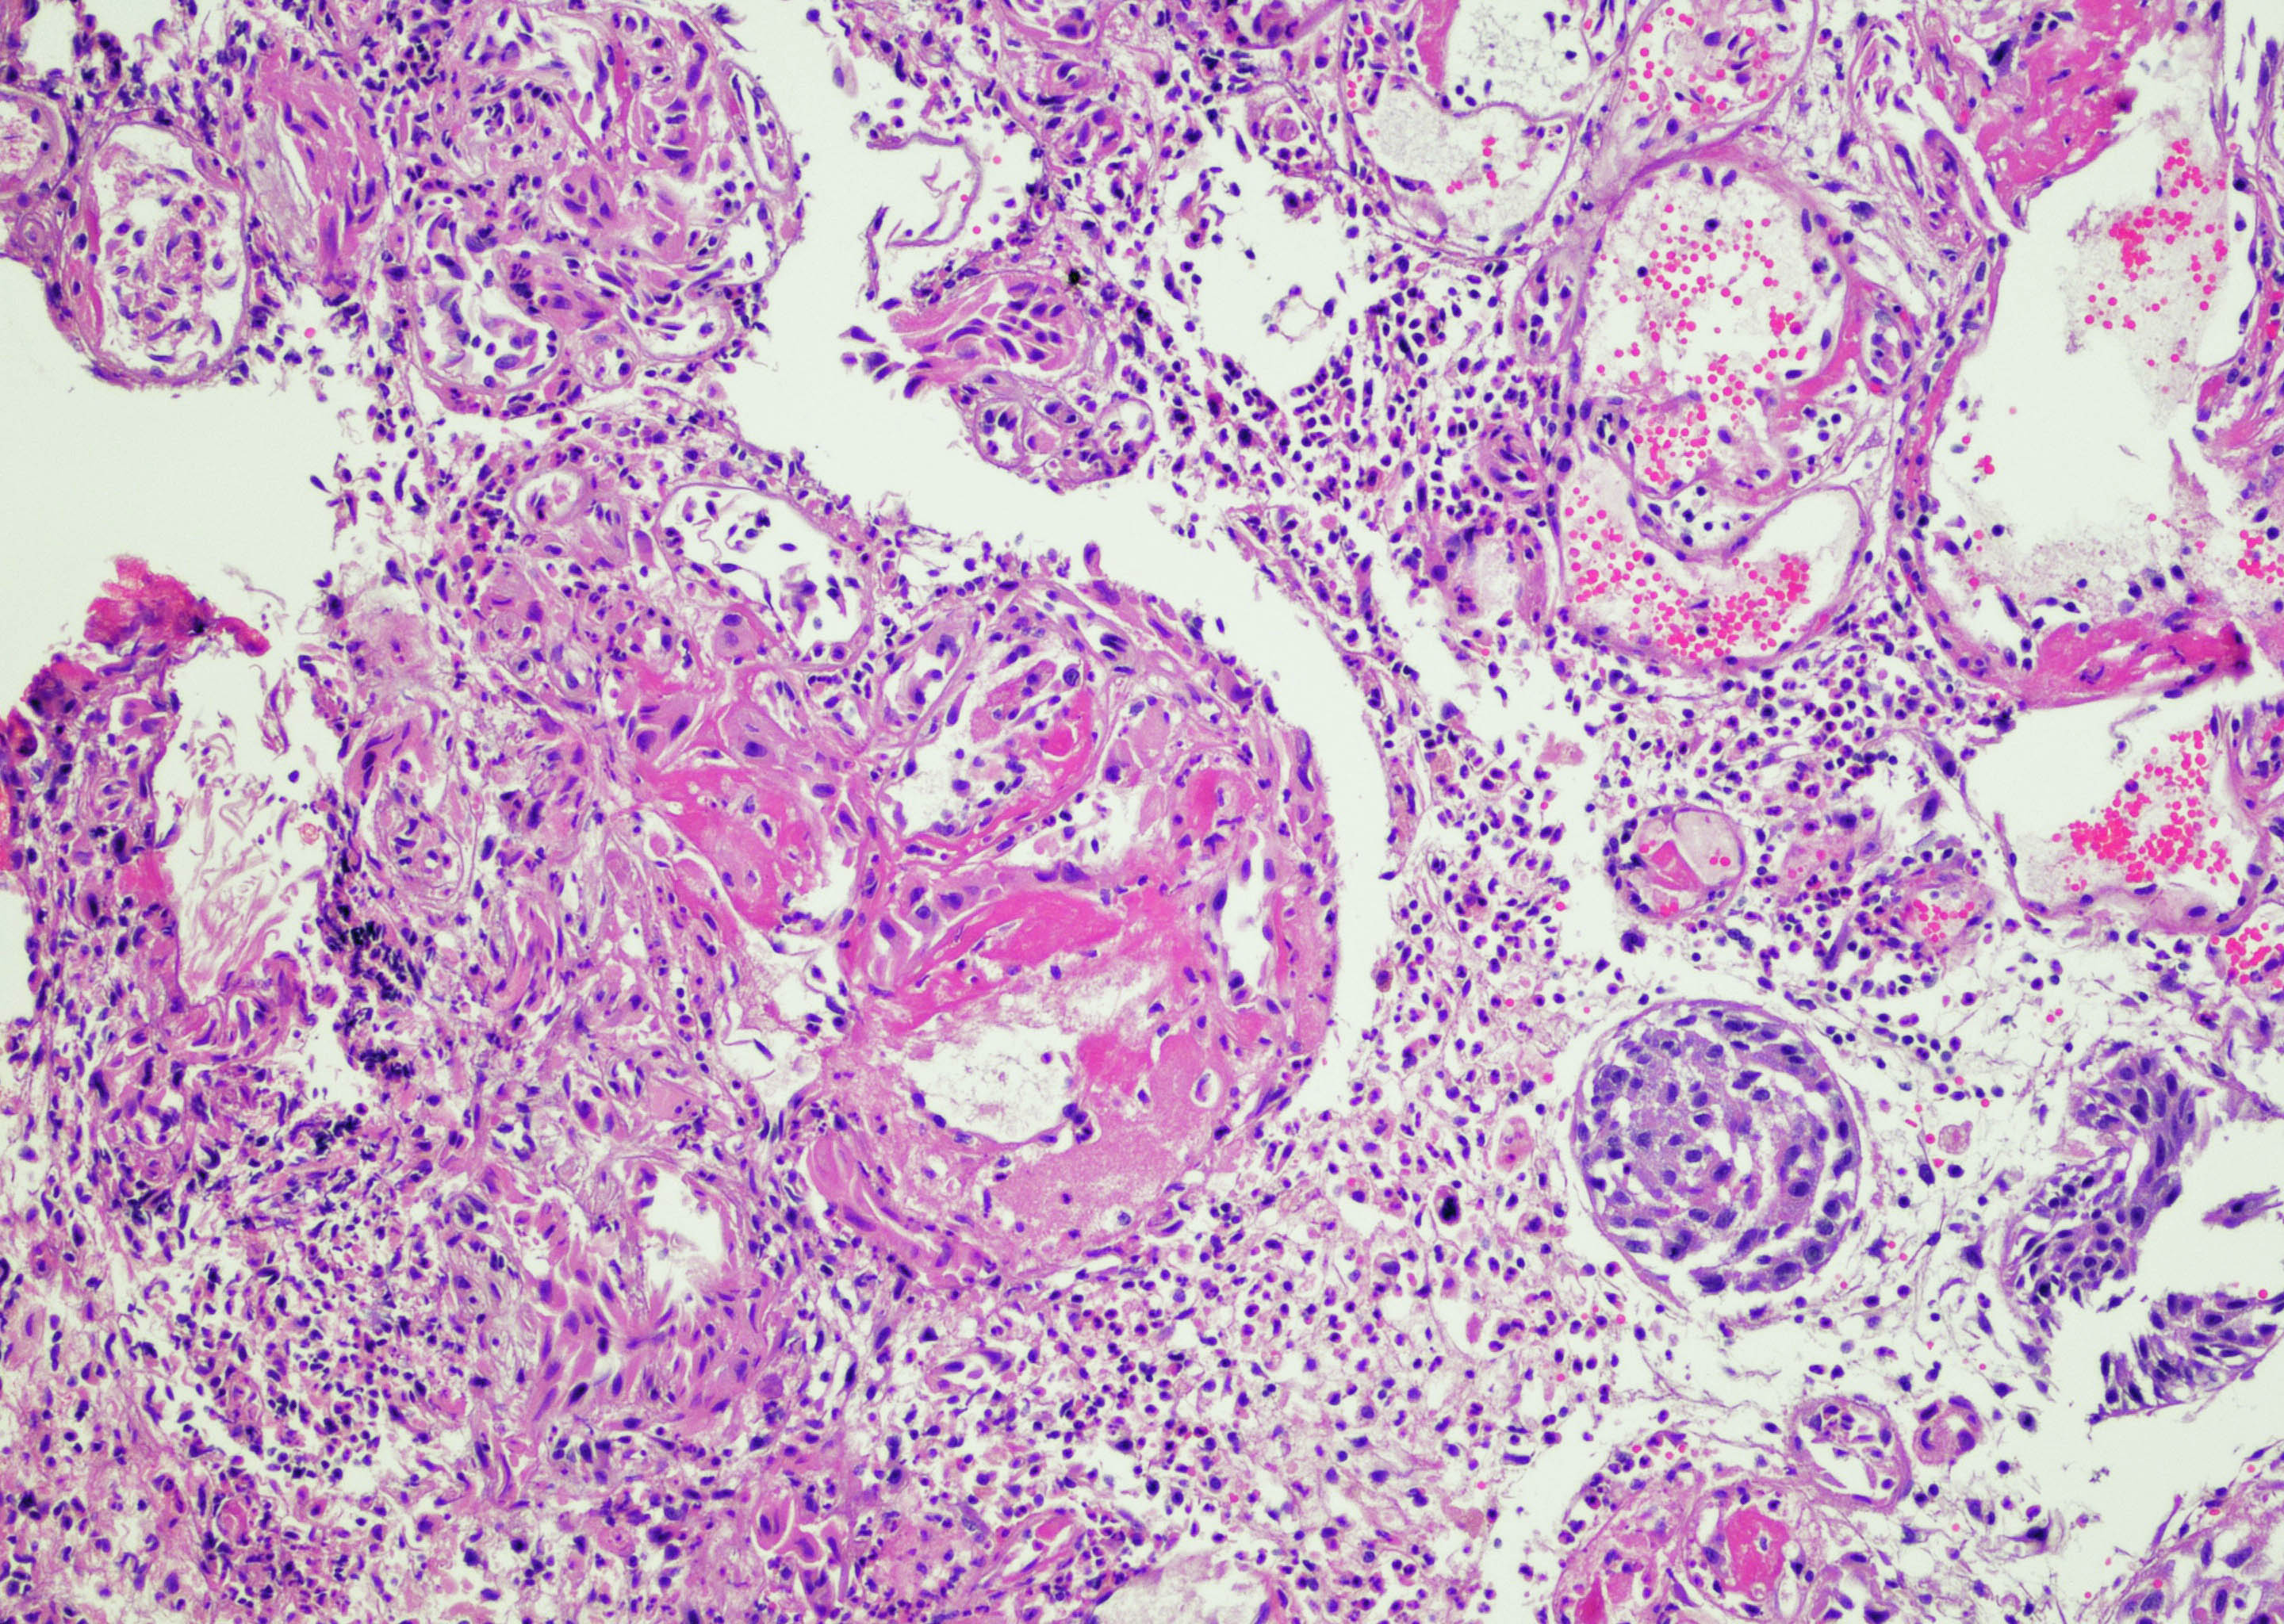

- Vessels with fibrin thrombi, fibrinoid vascular necrosis, vascular congestion, thickened walls, endothelial proliferation and telangiectasia

- Acute and chronic inflammation

- Reactive multinucleated stromal fibroblasts with smudgy nuclei

- Fibrosis and edema

- Hemorrhage and hemosiderin

- Pseudocarcinomatous urothelial hyperplasia: variable sized urothelial cords and nests with rounded or irregular edges present in the lamina propria and enclose dilated blood vessels with fibrin deposition (Am J Surg Pathol 2008;32:92)

- Acute phase: edematous, congested and telangiectatic vessels, acute and chronic inflammatory infiltrate, atypical stromal cells with multinucleated forms

- Chronic phase: atrophic urothelium, atrophic smooth muscle layer, collagen deposition (fibrosis) (Am J Surg Pathol 2004;28:909)

Microscopic (histologic) images

Contributed by Y. Albert Yeh, M.D., Ph.D. and Jennifer Lee, M.D.

- Comment: There is a history of radiation therapy per the medical record. The transurethral resection of the bladder lesion shows fragments of urothelial mucosa with total and partial denudation of urothelium. The urothelial lining cells show reactive changes. There is marked edema, hemorrhage and mixed inflammatory infiltrate composed predominantly of neutrophils and lymphocytes in the lamina propria. Reactive multinucleated stromal fibroblasts are seen. Telangiectatic vessels with fibrinoid necrosis and intravascular fibrin deposition are seen. Anastomosing cords and nests of urothelial cells encircling the vessels with fibrin deposition is evident. Urothelial cells with hyperchromatic nuclei, increased nuclear to cytoplasmic ratio and prominent nucleoli are seen. These features are consistent with radiation cystitis with pseudocarcinomatous urothelial hyperplasia. Muscularis propria is not identified in this specimen.

- Invasive urothelial carcinoma (Am J Surg Pathol 2004;28:909):

- Absence of urothelial nests surrounding ectatic vessels with intravascular and stromal fibrin deposition

- More prominent urothelial atypia

- Usually without pronounced acute and chronic inflammation

- Invasion of muscularis propria (if present) is most diagnostic

A 68 year old man presented with hematuria and dysuria. He has a medical history of prostate cancer that was treated with radiation therapy. Cystoscopy revealed hemorrhage in the right bladder wall. A transurethral resection of the lesion was performed. A photomicrograph is shown above. What is the diagnosis?

- Radiation cystitis with pseudocarcinomatous hyperplasia

C. Radiation cystitis with pseudocarcinomatous hyperplasia. Answers A, B and D are incorrect because anastomosing cords and nests of urothelial cells encircling ectatic vessels with intravascular and stromal fibrin deposition in a background of mixed inflammation are not present in these entities.